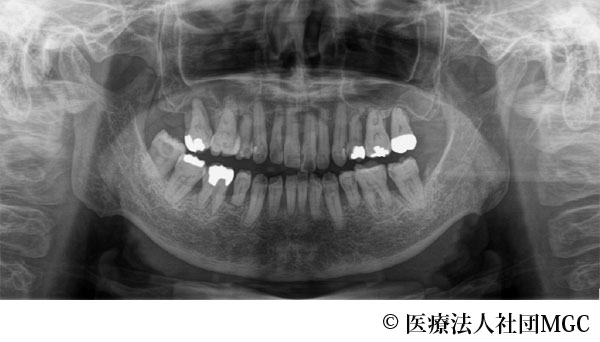

【症例3】上下All-on-4(オールオンフォー)

- 治療前

- 治療後

- 治療名

- 上下All-on-4(オールオンフォー)

- 費用

- 5,888,300円(税込)

- 期間

- 6ヵ月

治療内容

患者様の症状

上のブリッジが取れたことをきっかけに、全体に歯をきれいにしたいとご来院されました。

治療法

ご相談の結果、患者様の生活の質(QOL)を向上させ、しっかり噛め、審美的にも重視した、上下All-on-4(オールオンフォー)を行いました。

治療結果

機能性、審美性ともに改善し、満足していただけました。

※治療結果は患者様によって個人差があります。

治療を行う上での注意点(リスク・副作用)

インプラント周囲炎の可能性、まれに歯が欠ける可能性があります。